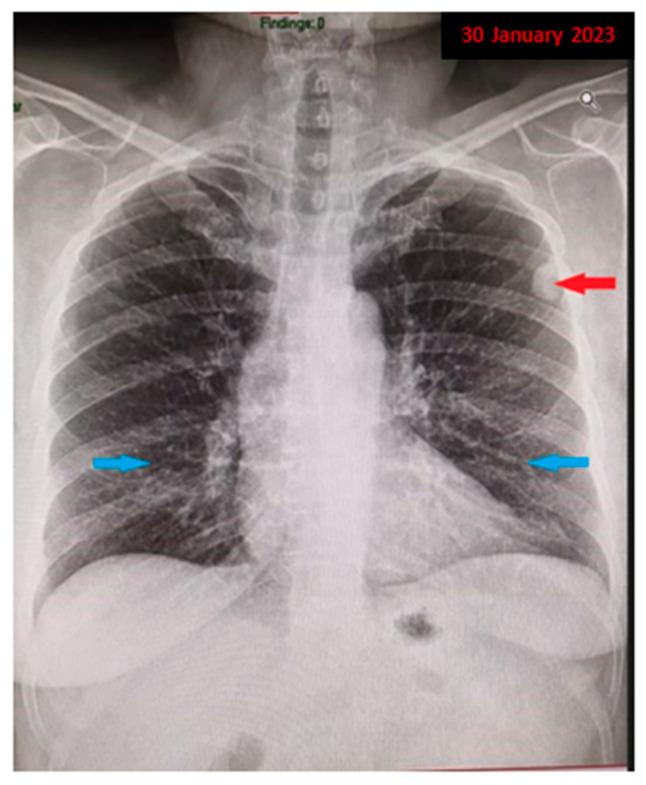

We report the case of a 59-year-old female patient, a former smoker, who was diagnosed with bilateral pulmonary nodules. Extensive medical investigations were conducted, including a surgical lung biopsy, which led to the diagnosis of pulmonary amyloidoma. The diagnostic process was guided by the presence of a persistent, polymorphic, and nonspecific clinical picture, strengthened by imaging findings characterized by mixed nodular lesions and the addition of interstitial involvement, along with partial deterioration of the pulmonary parenchyma architecture. Although it is recognized as a benign tumor, pulmonary amyloidoma requires special care in order to rule out systemic involvement, association with lymphomas, or systemic amyloidosis. This case highlights the comprehensive investigations required in the presence of multiple pulmonary nodules and the wide range of possible diagnoses. It underscores the pivotal role of surgical lung biopsy and histopathological examination. The case is instructive, addressing a rare pathology, on the border between specialties, while also emphasizing potential evolving challenges and providing further insights into the clinical course of this disease.

我们报告了一例59岁的女性患者,她既往有吸烟史,被诊断为双侧肺结节。进行了广泛的医学检查,包括手术肺活检,最终诊断为肺淀粉样瘤。诊断过程以持续、多形性和非特异性的临床表现为指导,并通过以混合结节性病变为特征的影像学表现以及间质受累和肺实质结构部分恶化的情况得到强化。尽管肺淀粉样瘤被认为是一种良性肿瘤,但为了排除全身受累、与淋巴瘤的关联或系统性淀粉样变性,仍需要特别关注。该病例突出了在存在多个肺结节时所需的全面检查以及广泛的可能诊断。它强调了手术肺活检和组织病理学检查的关键作用。该病例具有指导意义,涉及一种罕见的病理学,处于各专业的交叉领域,同时也强调了潜在的不断演变的挑战,并为该疾病的临床过程提供了进一步的见解。